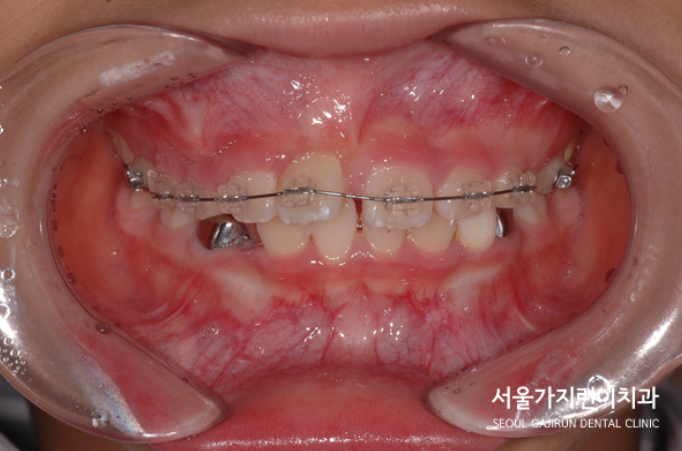

매복된 중절치 치료 결과

위 사진을 보면 달라진 모습을 확연하게 확인할 수 있었습니다. 치근 흡수 없이 가지런한 치아배열이 완성이 되었는데요. 비교적 8세의 나이에 일찍 발견하여 교정을 진행해 좋은 결과를 얻을 수 있었습니다. 만약 매복된 치아가 잇몸뼈와 유착이 심했다면 결국 치아가 내려오지 않았을 수도 있었는데요. 어린 나이에 발견해 유착 가능성이 낮은 탓에 온전한 자리를 찾아볼 수 있게 되었습니다. 상악 중절치와 매복을 비롯한 맹출 장애는 혼합치열기에 흔하게 발견할 수 있는데요. 유치 빠지고 영구치가 나는 시기에 교정치과를 찾아 검진해보면 바르게 성장하고 있는지를 체크할 수 있으니 성장기의 자녀가 있는 가족이라면 유심히 체크해보는 것도 좋겠습니다.